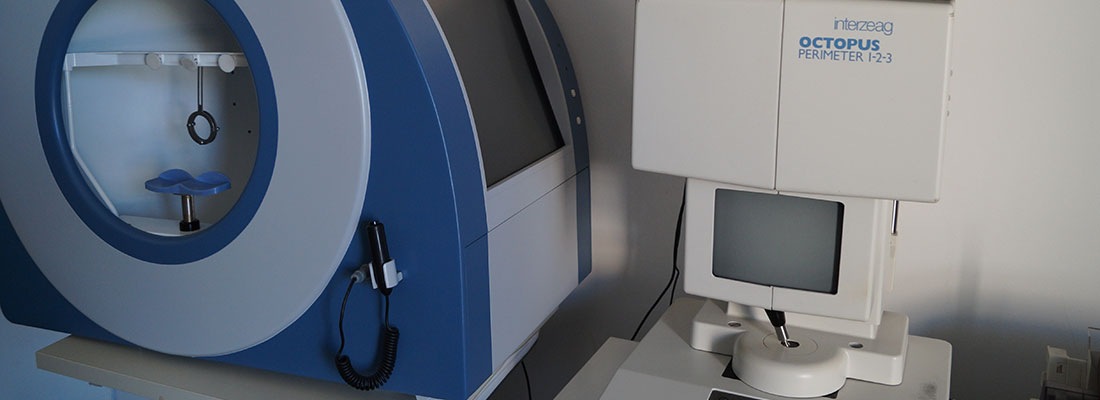

Διαθέτουμε σύγχρονα μηχανήματα για την διάγνωση και την παρακολούθηση παθήσεων ωχράς κηλίδος, γλαυκώματος κτλ.